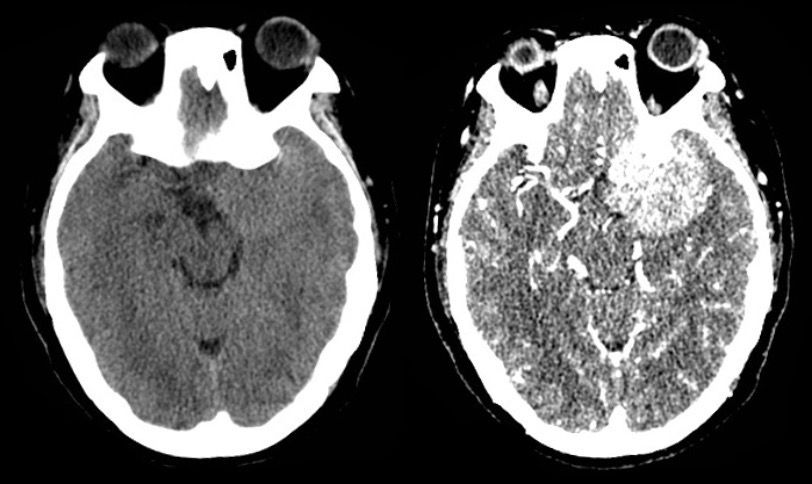

病例1:中年女性,48岁,因发作性头晕、左眼视物模糊半年入院

查体:神志清,对答可,双瞳等大同圆,对光反射正常,粗测视力 L 0.3/R 0.8 ,视野无缺损,无复视,眼球各方向活动正常,四肢肌力正常,深浅感觉正常,病理征(-)。

CT检查:

CTA检查:可见颈外动脉分支参与供血,颈内动脉颅内段及大脑中动脉分支受压移位。